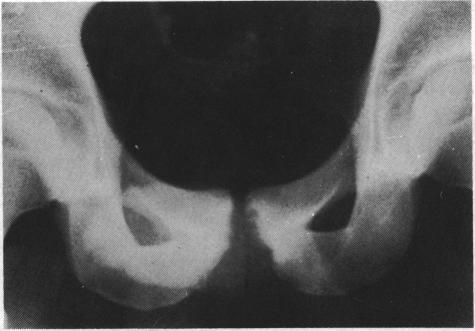

Associated factors in recurrent groin and hamstring injuries.

Br J Sports Med. 1982 Mar;16(1):37-9. doi: 10.1136/bjsm.16.1.37.